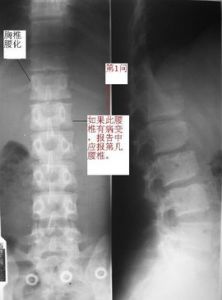

分為骨幹(diaphysis)、骨骺(epiphysis)、乾骺端(metaphysis)、骨骺板/線(epiphyseal plate or line)幾個部分。1. 骨幹(黑長箭) 骨皮質外面是外骨膜,為軟組織密度,故在X線片上不顯影。骨皮質含鈣多為骨密質。X線表現為密度均勻的緻密影,骨幹中部最厚,向兩端延伸性變薄,外緣光滑整齊。骨幹中央為骨髓腔,含造血組織和脂肪組織,X線表現為由骨幹皮質包繞的無結構的半透明區。

2. 乾骺端(黑短箭) 由松質骨組成,骨小梁彼此交叉呈海綿狀(骨紋理),周邊為薄的骨皮質。頂端為一橫形薄層緻密影,為乾骺端的臨時骨化帶,是骨骺板軟骨位乾骺端軟骨基質的鈣化,經軟骨內成骨即為骨組織代替,形成骨小梁,經改建塑形變為乾骺端松質骨結構。此臨時鈣化帶隨著軟骨內成骨而不斷向骨骺側移動,骨即不斷增長。骨幹與乾骺端間無清楚分界線。

3. 骨骺(白長箭) 在胎兒及兒童時期多為軟骨,即骺軟骨,X線片上不顯影。骺軟骨有化骨功能,在骨化初期於骺軟骨中出現一個或幾個二次骨化中心,即骺核。X線表現為小點狀骨化影。骺軟骨不斷增大,而骺核也不斷骨化增大,形成松質骨,邊緣由不規則變為光整。X線片上,常將這樣的骺核稱之為骨骺,其邊緣仍有薄層軟骨。骨骺的乾側軟骨成骨逐漸停止,形成一層薄的骨質,為骨骺終板,X線表現為一條骨性緻密影。

骨骺4. 骨骺板/線(白短箭) 當骨骺與乾骺端不斷骨化,兩者間的軟骨呈板狀時,則稱為骨骺板。隨著骨的生長,骨骺軟骨板逐漸變小呈線狀結構,X線片上呈橫形透明線,位於骨骺與乾骺端之間,稱之為骺線。最後骨骺線消失,即骨骺與骨幹結合,完成骨的發育。X線表現為骺線消失。